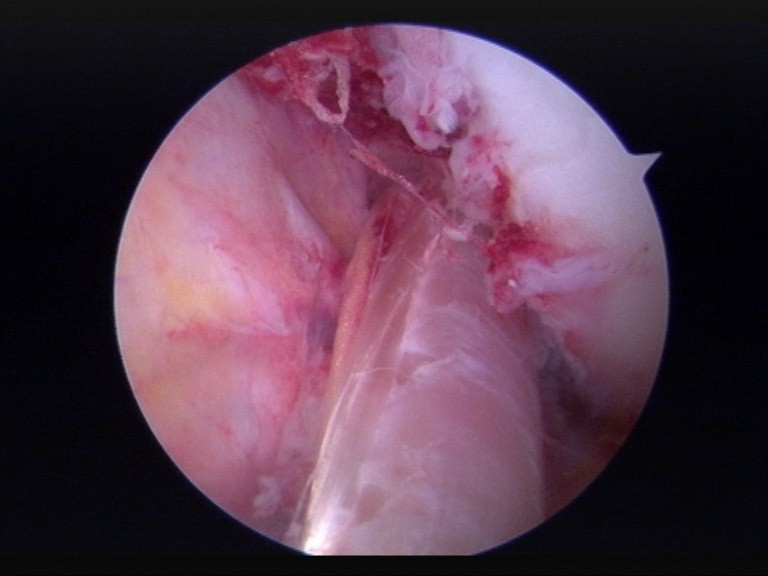

Die Operation wird arthroskopisch durchgeführt, wobei auf die Ansprüche des Patienten eingegangen wird. Der Ersatz des vorderen Kreuzbands erfolgt durch Entnahme der Semitendinosus und Gracilissehne. Bei ausreichender Sehnenlänge wird danach die Rekonstruktion in der Double-Bundle-Technik durchgeführt. Da das vordere Kreuzband aus zwei Bündeln, einem anteromedialen (am), welches das Verschieben des Unterschenkels gegenüber dem Oberschenkel verhindert, und einem posterolateralen (pl) Bündel, welches für die Rotationsstabilität verantwortlich ist, besteht, ist eine Wiederherstellung beider Bündel zu erstreben.